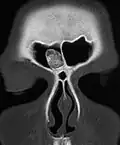

An osteoma (plural osteomas or less commonly osteomata) is a new piece of bone usually growing as a benign tumour on another piece of bone, typically the skull. When grown on other bone it is known as "homoplastic osteoma"; on other tissue it is called "heteroplastic osteoma".[1]

Osteoma represents the most common benign neoplasm of the nose and paranasal sinuses. The cause of osteomas is uncertain, but commonly accepted theories propose embryologic, traumatic, or infectious causes. They are present in Gardner's syndrome.

Larger craniofacial osteomas may cause facial pain, headache, and infection due to obstructed nasofrontal ducts. Often, craniofacial osteoma presents itself through ocular signs and symptoms (such as proptosis).[2]